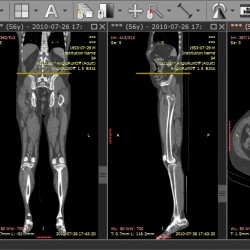

- Производится тщательное обследование сустава на предмет хронических изменений и травматических повреждений